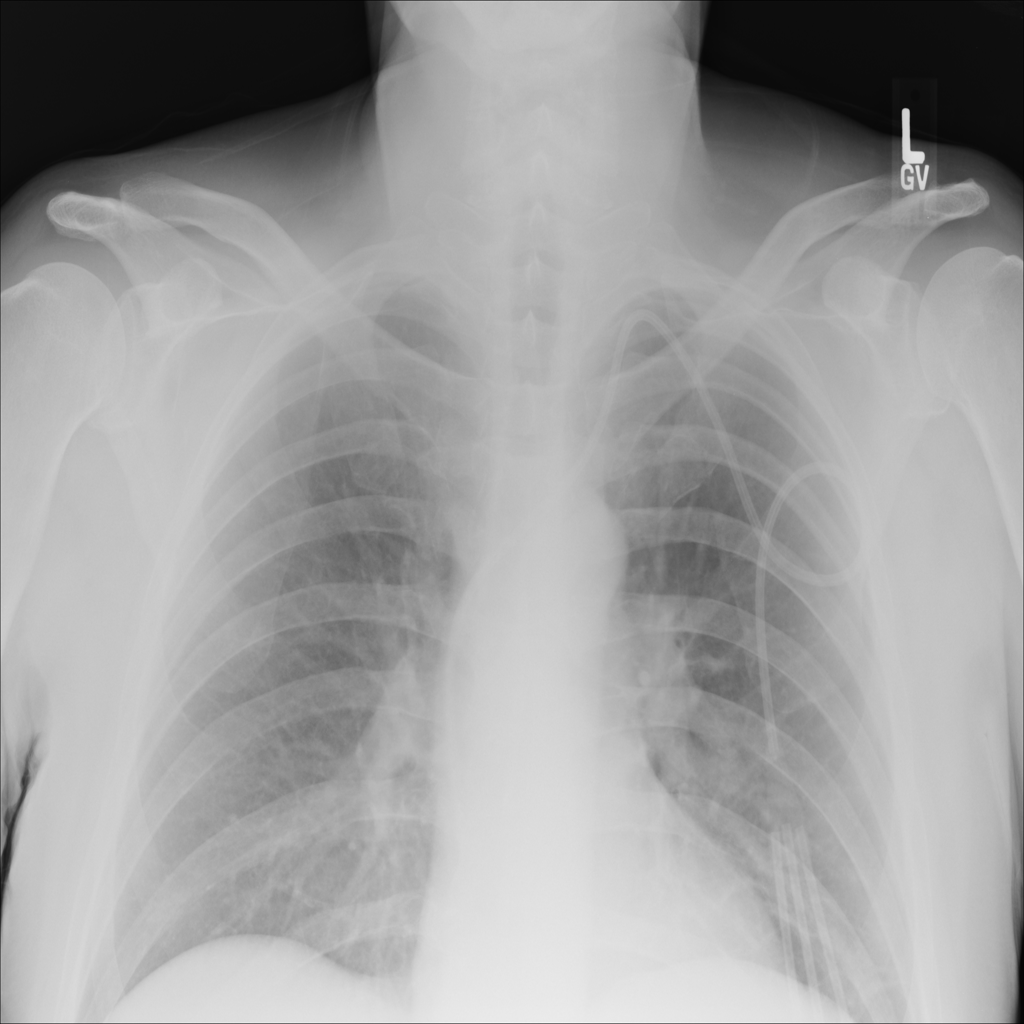

PAT-E828 · IMG-005Edema

PAT-E828 · IMG-005

AP